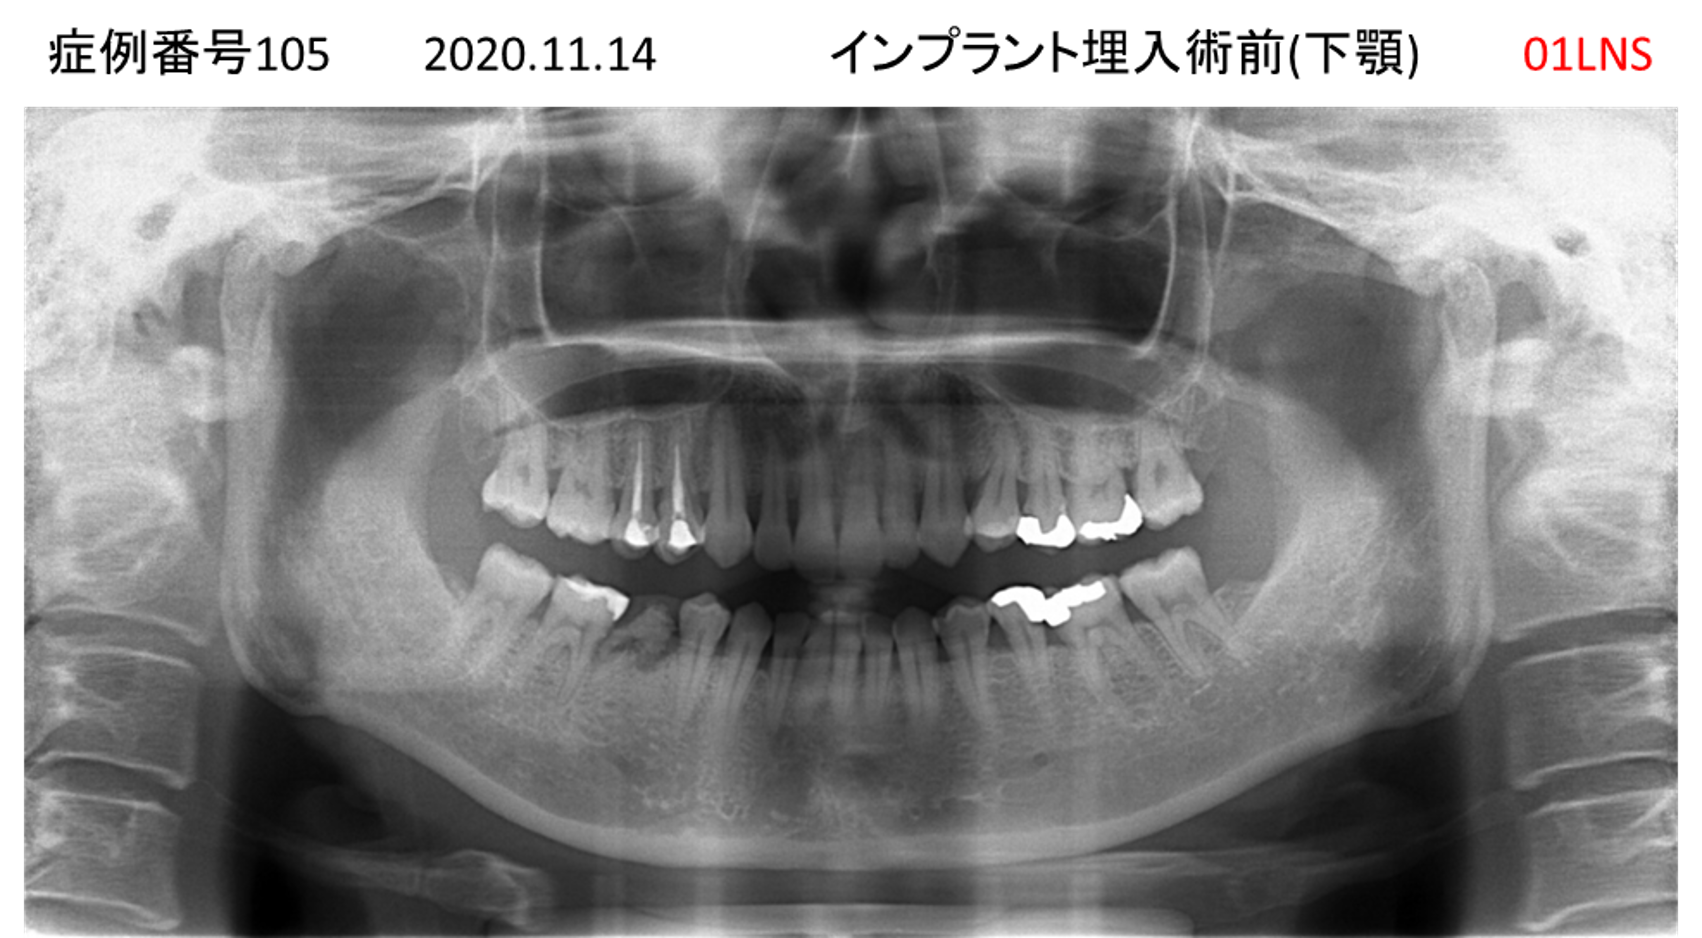

奥歯で噛めない患者様のインプラント症例

| 治療名称 |

インプラント |

| 治療費用 |

365万円+税 |

| 治療期間 |

5か月 |

| 患者さんの症状(主訴) |

奥歯で噛めない。上の前歯が揺れてきた。 |

| 治療内容 |

抜歯即時インプラント |

| 治療結果 |

食事に困らない。見た目がとても良くなった。 |

| 治療の注意点(リスク/副作用) |

インプラントが壊れたら再治療が必要 |